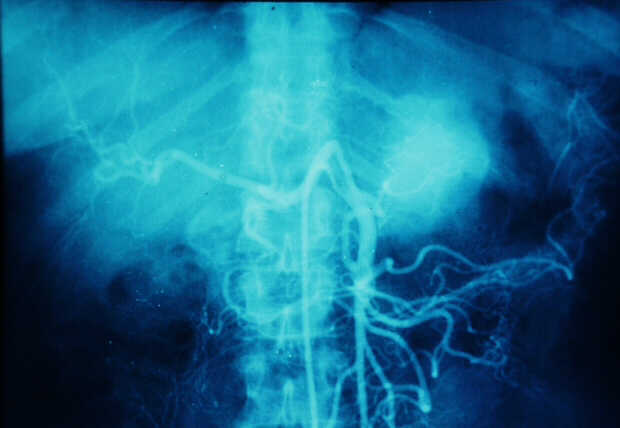

Diagnosis: Angiography

Giuseppe Morelli Coppola, Raffaella Niola, Franco Maglione

Unità Operativa di Radiologia Vascolare ed Interventistica, Azienda Ospedaliera "A. Cardarelli". Napoli, Italy